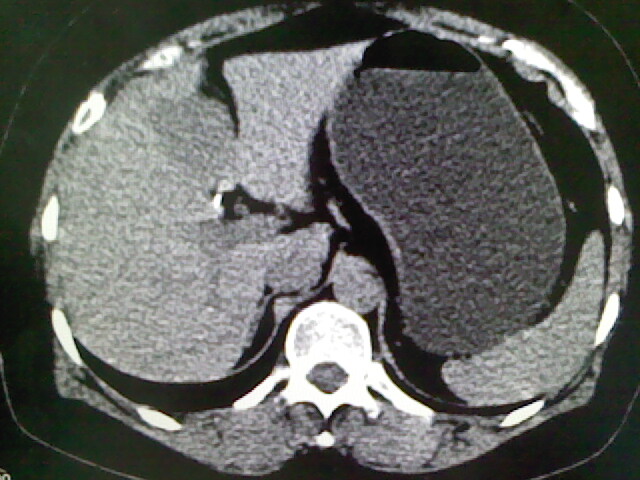

以下是引用卜一在2009-4-2 13:26:00的发言:[br]胆囊颈部结石伴胆囊炎!另:建议增强,待除外肝内占位及胆囊占位!

以下是引用liaoqiang在2009-4-2 16:23:00的发言:[br]胆囊是否切除?胆囊颈区致密影考虑金属夹?结石?肝脏右叶低密度影,考虑增强。